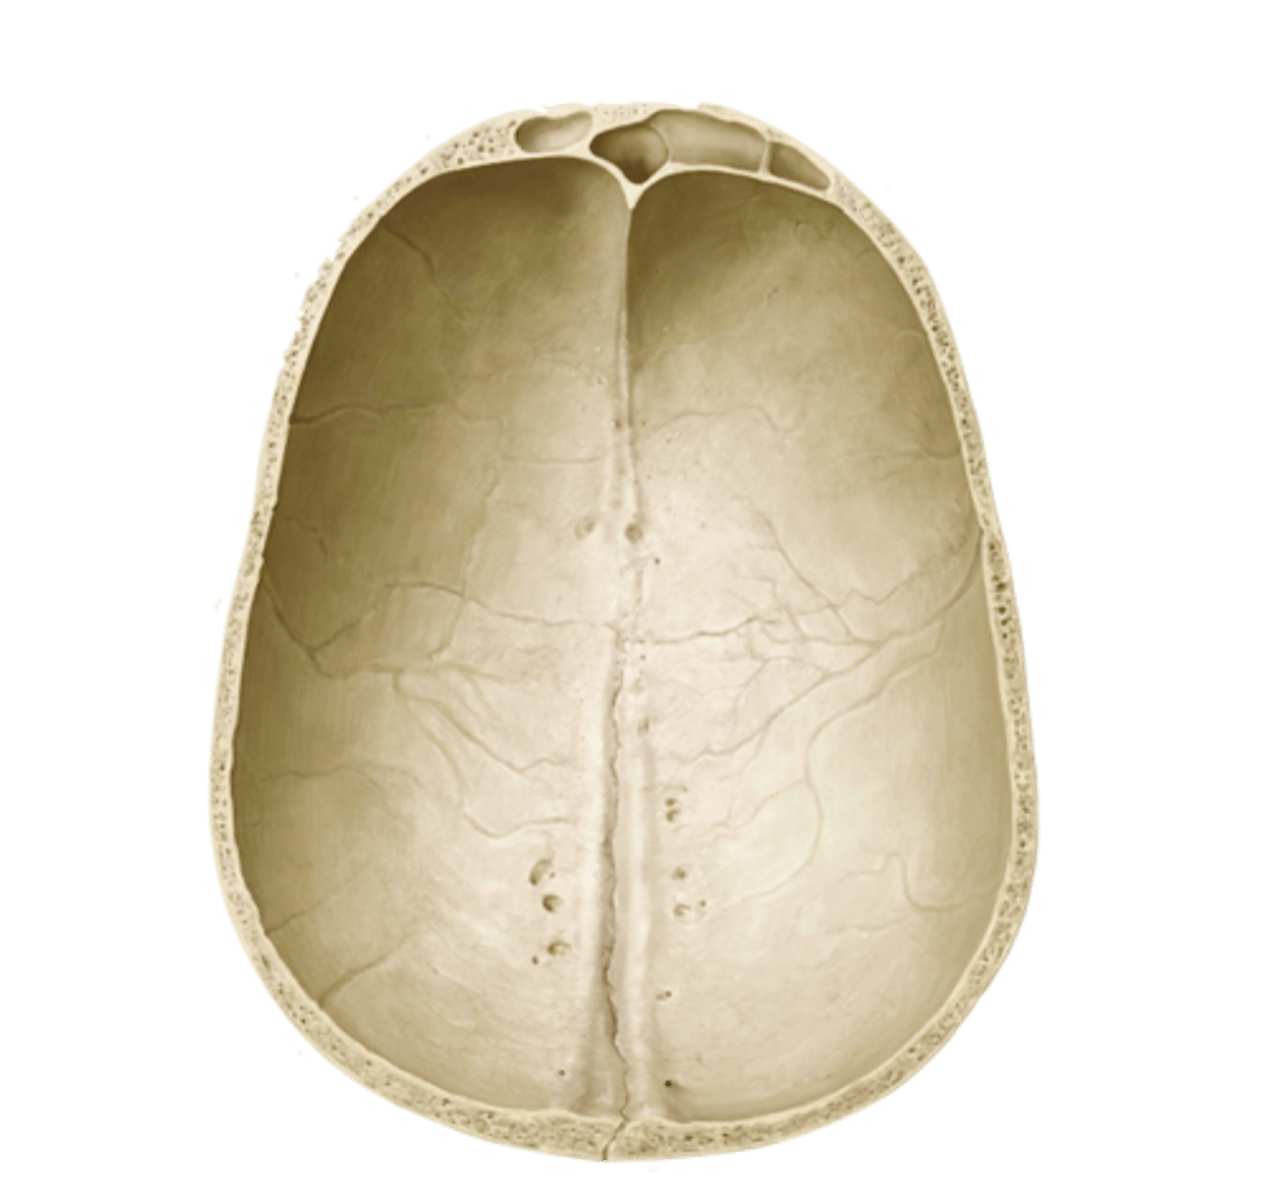

calvaria

roof of the neurocranium

coronal suture

sagittal suture

lambdoid suture

squamous suture

suture

interlocking line of union between bones